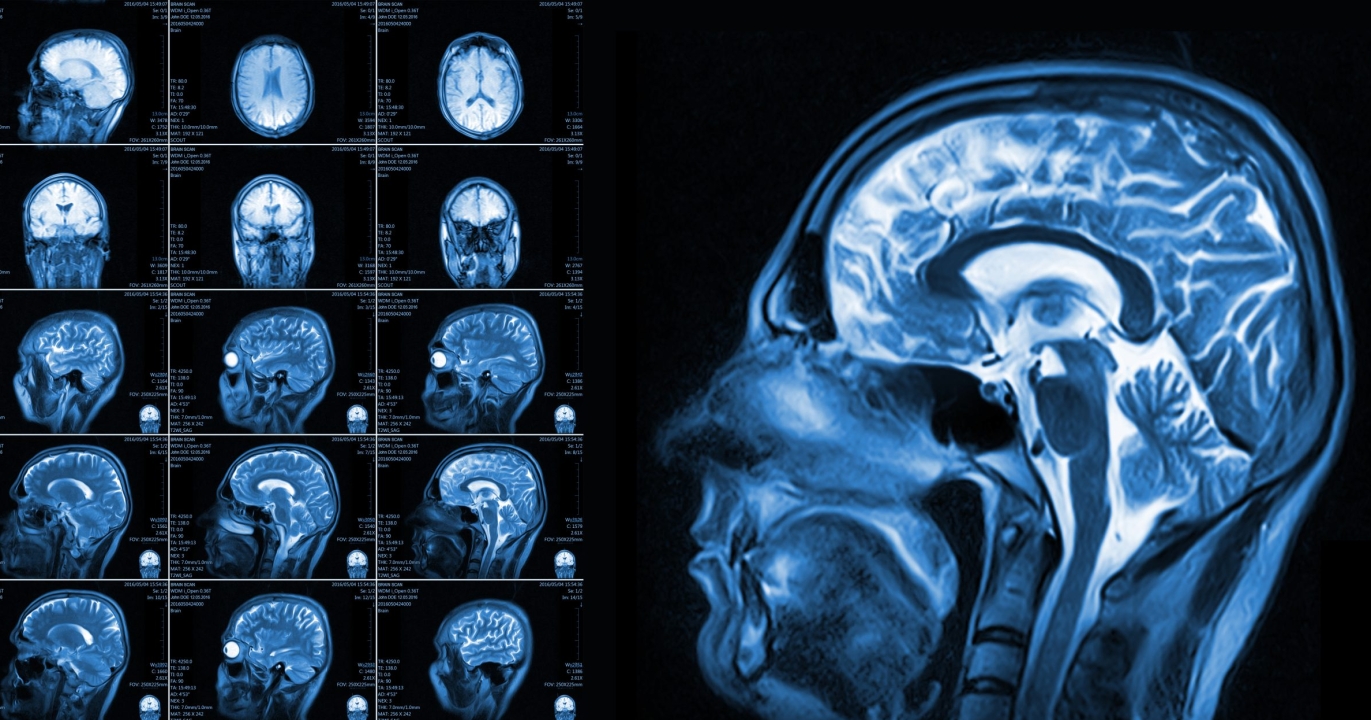

La question de ce qui se passe dans notre cerveau au moment de la mort fascine scientifiques et grand public depuis des siècles. Récemment, une équipe de chercheurs a utilisé des techniques avancées de scan cérébral pour simuler l’expérience de la mort et observer ce qui se produit dans le cerveau humain lors de cette ultime transition. Cette étude inédite ouvre une fenêtre sur les processus neurologiques qui accompagnent la fin de la vie et soulève de nouvelles questions sur la conscience et l’expérience de mort imminente.

Les chercheurs ont utilisé l’imagerie par résonance magnétique fonctionnelle (IRMf) pour surveiller l’activité cérébrale de volontaires soumis à une simulation de mort clinique. Cette approche permet de mesurer en temps réel les changements dans les zones du cerveau responsables de la conscience, de la mémoire et des émotions.